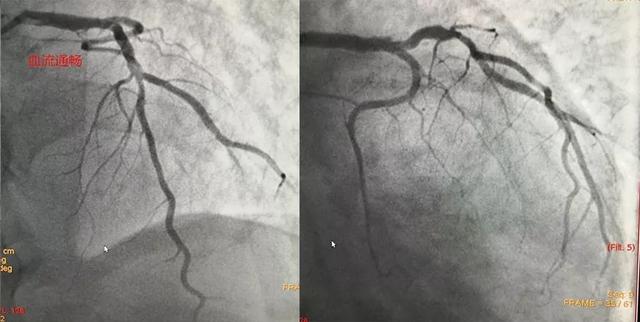

左主干闭塞(图左)右冠正常(图右)

考虑到残余狭窄不严重,血流已经达到3级的正常程度,当时我们就没有植入支架。

半月后我们重新复查造影如下:

血管通畅,无明显狭窄,未植入支架。